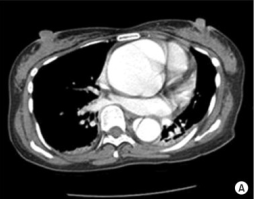

What's the Diagnosis?

Guess 1 / 5